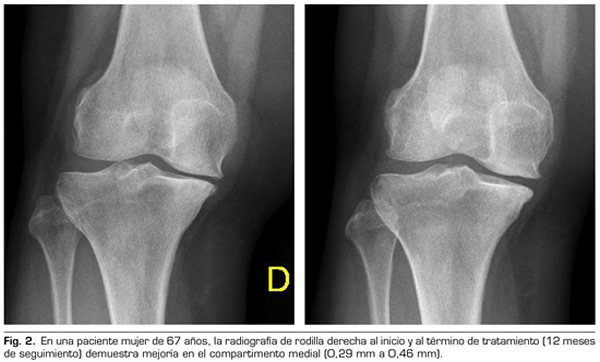

Con respecto a las variables radiológicas, al valorar a 53 de los 115 pacientes que cumplieron un año de seguimiento después del tratamiento con ozono, se observó que el compartimento interno aumento significativamente de 4,12 ± 1,41 mm a 4,4 ± 1,35 mm (p = 0,0008) y el compartimento externo aumentó de 6 ± 1,37 a 6,16 ± 1,4 mm (p = 0,0753) (Tabla II). Se presentan 2 casos clínicos como muestra del cambio radiológico en los compartimentos interno y externo (Figuras 2 y 3).

Para la evaluación radiográfica de la articulación tibiofemoral medial y lateral, se realizaron radiografías bilaterales anteroposteriores, con ambas piernas apoyadas y completamente extendidas, en carga según protocolo estandarizado (9). Todas las imágenes radiográficas se adquirieron digitalmente mediante un sistema de comunicación de archivo de imágenes (PACS). Se evaluó a 53 pacientes de los 115 que cumplieron un año de seguimiento tras la primera infiltración. Se midió la distancia femorotibial en la radiografía en los compartimentos medial y lateral en la distancia percibida como la más estrecha del espacio articular, y utilizando el programa de medición PACS. Todas las evaluaciones fueron llevadas a cabo por un solo autor, con el fin de reducir la variación interobservador, cuyo coeficiente de variación para medidas repetidas es 3-8 % (9,10).